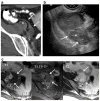

The appendix may demonstrate a perplexing range of normal and abnormal appearances on imaging exams. Familiarity with the anatomy and anatomical variants of the appendix is helpful in identifying the appendix on ultrasound, computed tomography, and magnetic resonance imaging. Knowledge of the variety of pathologies afflicting the appendix and of the spectrum of imaging findings may be particularly useful to the emergency radiologist for accurate diagnosis and appropriate guidance regarding clinical and surgical management. In this pictorial essay, we review appendiceal embryology, anatomical variants such as Amyand hernias, and pathologies from appendicitis to carcinoid, mucinous, and nonmucinous epithelial neoplasms.